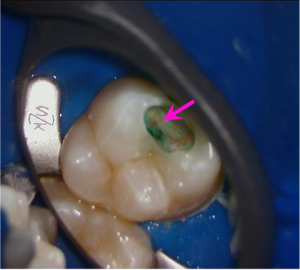

虫歯治療中のマイクロスコープでの写真です。

唾液の混入防止(唾液には細菌がおりこれを排除しないと口の中で無菌に近い環境を保てません)でラバーダムを装着しております。

上の写真は染色する液で虫歯を染めています。虫歯は残っています(青色部)が、矢印の部分には神経が透けています。